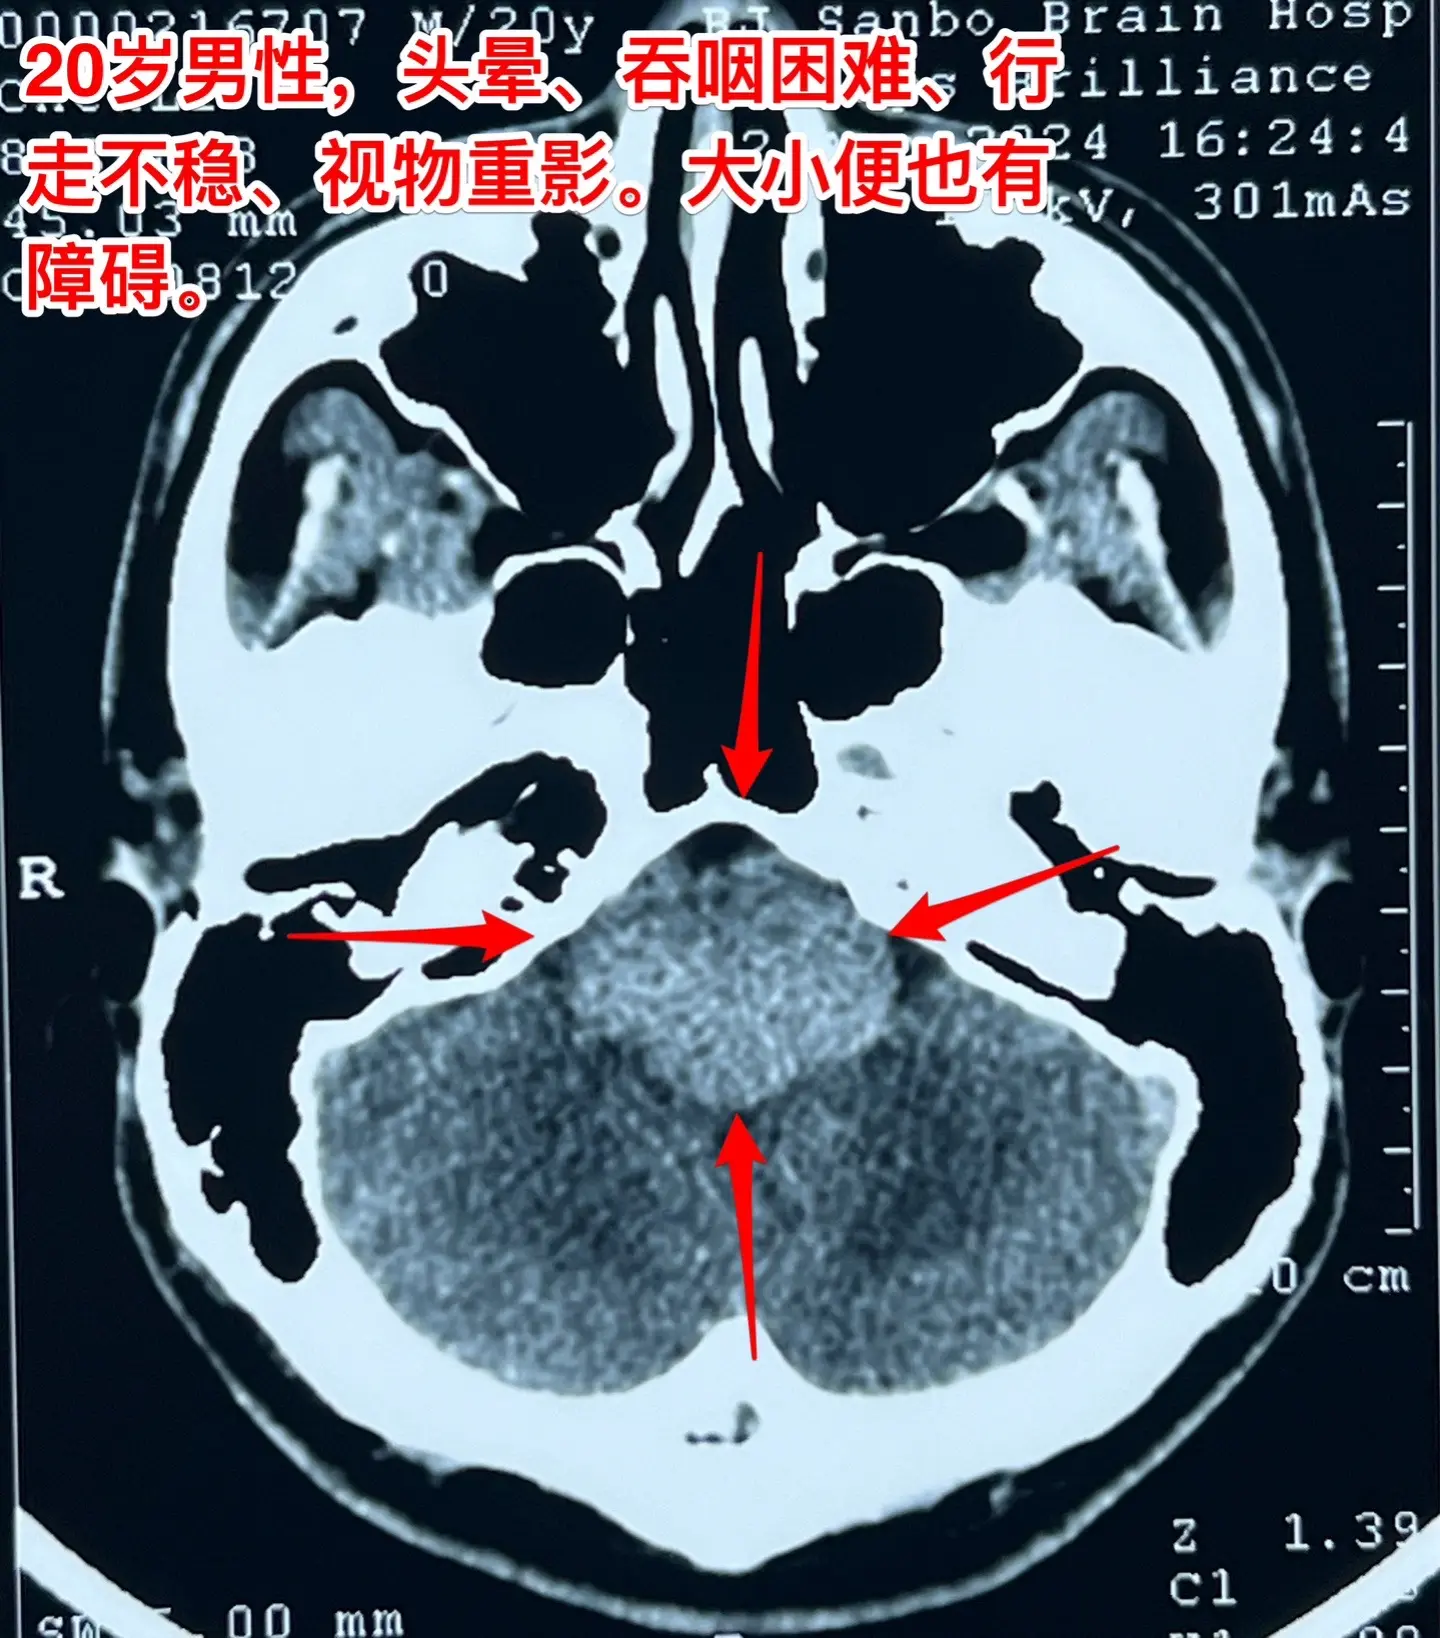

头晕、吞咽困难、行走不稳、大小便障碍。20岁漳州的小伙子,2个月前出现头晕,一个月前出现吞咽困难,半个月个月前出现多睡,一周前出现行走不稳、视物重影、发音不清晰,而且有大小便障碍。 一般人认为这些症状都是七八十岁的老人才会有的,怎么会出现在20岁的年轻人身上呢?他到底得了什么病? 磁共振和CT显示脑干腹侧有一个巨大囊肿,对脑干有明显的压迫,考虑为肠源性囊肿。针对这个病,只有选择作手术切除囊肿,病人的症状才有希望好转。 2024.8.14作了手术,术中看见囊壁与脑干的神经、基底动脉的分支血管粘连。切除大部分囊壁,清除了囊内容物,脑干得到充分减压。 手术后病人的症状显著改善了!